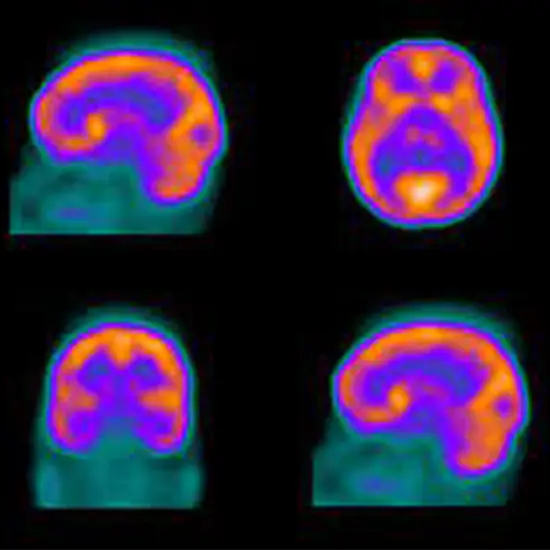

Thalbrain Spect (Thallium brain single-photon emission computed tomography) -REC/R is a nuclear medicine ) imaging scan reliably evaluates blood flow and activity in the brain. This scan is useful in brain tumor detection because the areas of concern light up on the images.